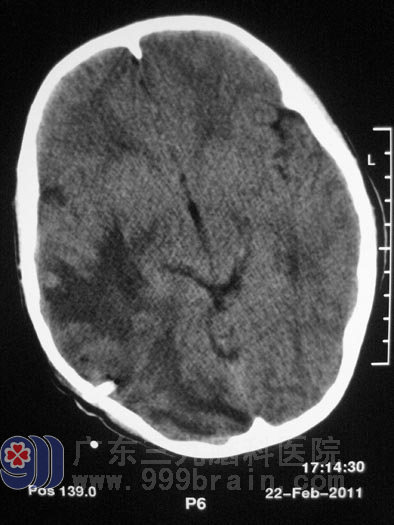

俗话说:屋漏偏逢连夜雨,船迟又遇打头风。几个月前小马无明显诱因开始头痛,呈胀痛感,当时无发热,到当地医院以感冒对症处理后症状稍缓解,但之后反复头痛发作,间断呕吐。1月前小马突发高热,体温达39度,入当地医院行头颅MR示“双侧大脑半球多发占位,脑水肿明显,考虑多发脑脓肿可能”,医生建议手术治疗,但考虑到小马情况特殊,加上当地医院医疗设备、技术都不能保证,所以不敢冒然手术。“十多年来我们都没有放弃,难道现在就这样放弃了?”小马的父亲越想越不甘心,遂开始四处打听,经一朋友介绍得知了广东三九脑科医院,父子一行人挎上包裹,踏上求医的路程。

脑脓肿

广东三九脑科医院神经外五科鲁明主任检查小马后,发现他颅内压比正常人稍高,心脏彩超示“先天性心脏病,室间隔缺损”, 二尖瓣听诊区可闻收缩期杂音,鲁主任同全院资深专家会诊后一致认为小马可以耐受手术。2011年2月22日小马被送入手术室行“右侧顶枕叶脑脓肿穿刺引流术”,术中严密监测心电变化,尽量减少手术时间,术中见黄绿色脓液涌出,反复冲洗脓腔,术中出血少,术程顺利。术后并没有放松警惕,继续予罗氏芬冲洗脓腔,继续抗感染、营养心肌、止血对症支持治疗。当我们见到小马时,他已康复了,小马的父亲拉着医生的手激动地直说谢谢。